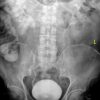

– Thận đôi (Duplex kidney): 2 đài bể thận riêng biệt thoát ra từ 1 thận.

– Đường bài xuất đôi (Duplex collecting system):

+ Niệu quản đôi (Double ureter): 2 đài bể thận với 2 niệu quản riêng biệt đổ vào bàng quang.

=> Hệ niệu đôi hoàn toàn: 2 đài bể thận và 2 niệu quản riêng biệt. Với hệ niệu đôi hoàn toàn, niệu quản dưới thường cắm vào bàng quang ở vị trí bình thường nhưng theo chiều vuông góc với thành bàng quang => làm cho niệu quản dưới hay bị trào ngược. Niệu quản trên cắm vào bàng quang ở vị trí thấp hơn và ở trong so với vị trí bình thường => đầu tận của niệu quản thường phồng lên trong lòng bàng quang tạo thành nang niệu quản với một miệng hẹp đổ vào lòng bàng quang